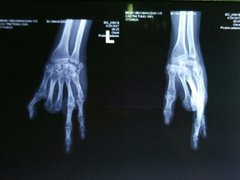

Lấy ngón chân ghép thành ngón tay cho nam công nhân

Nam công nhân 24 tuổi quê Hậu Giang bị đứt lìa bốn ngón tay do tai nạn lao động, được bác sĩ mổ ghép ngón...